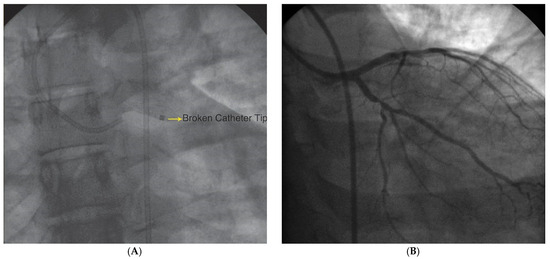

Der 70-jährige Patient wurde uns zugewiesen zur stationären kardialen Rehabilitation bei St. n. mechanischem Aortenklappenersatz wegen schwerer degenerativer Aortenstenose.[...]